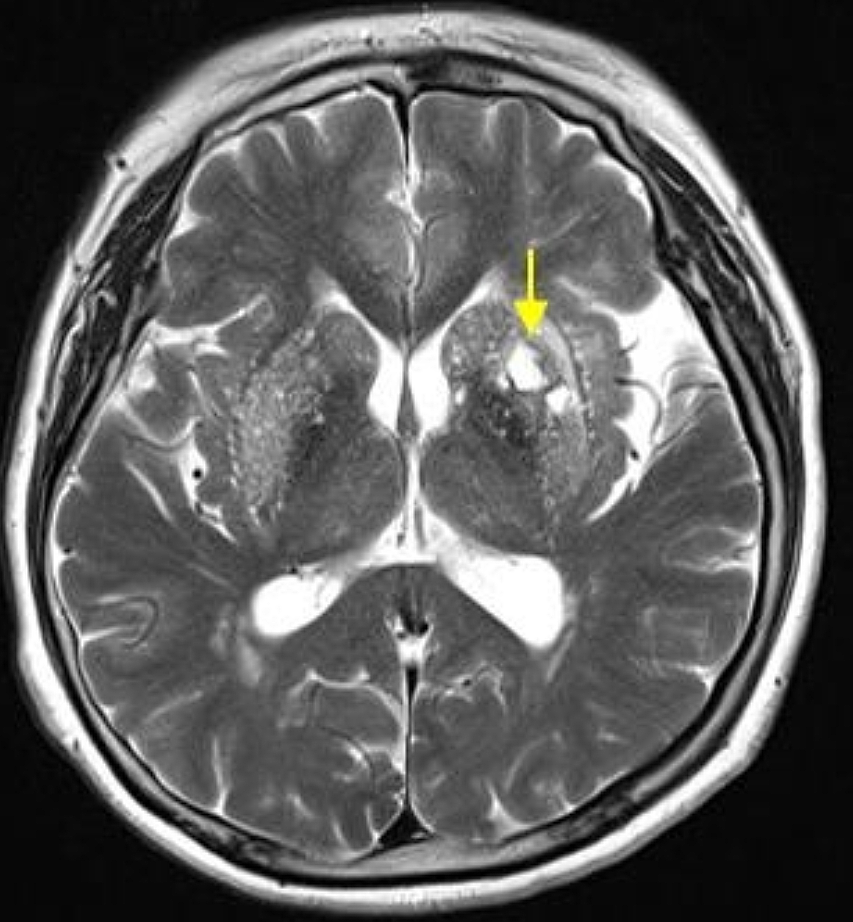

전조증상이 발현되면 뇌졸중 예방과 선제적 치료를 위해 MRI 검사 등 정확한 진단을 받습니다. MRI 검사는 예전과 다르게 뇌질환으로 의심되는 신경학적 증상이 있는 환자는 모두 사비의 부담 없이 뇌질환 예방 검진이 가능하게 되었습니다. 뇌졸중으로 진단받았다면 증상 정도와 환자 상태에 따라 약물치료, 내과적 시술, 외과적 수술을 시행합니다. 최근에는 중재적 시술이 발달해 골든타임안에 내원하면 막힌 혈관 내에 스텐트라는 그물망을 삽입해 혈전을 제거하는 뇌혈관 중재술을 통해 후유증을 줄이며 효과적으로 치료하는 방법도 있습니다.